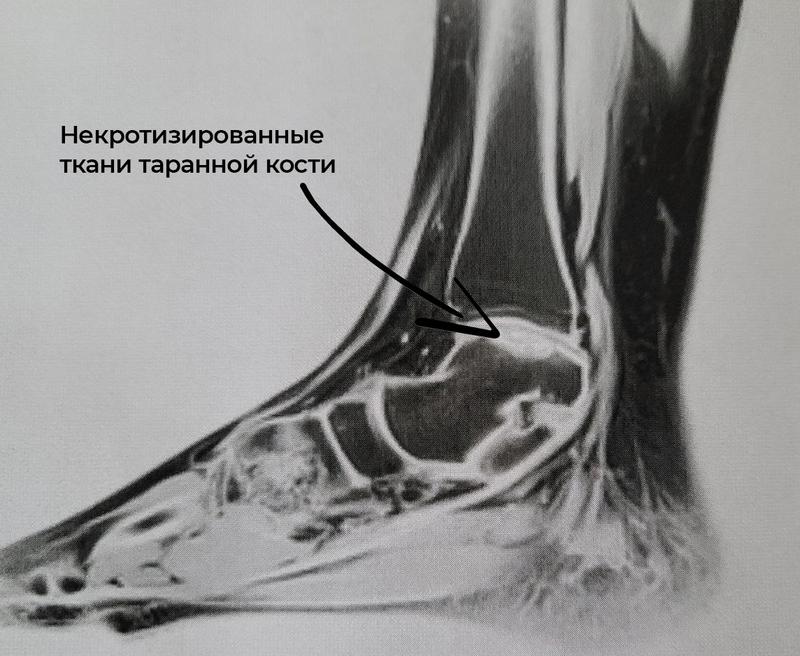

Врачи клиники Самарского госмедуниверситета избавили девочку-подростка от хромоты и боли - медики по новой методике провели операцию на стопе с асептическим некрозом таранной кости. Методику операции разработал травматолог-ортопед Василий Кузнецов. У 15-летней пациентки были жалобы на боли в области голеностопного сустава и хромоту. Проведя диагностику, врачи отделения выяснили, что у девочки асептический некроз таранной кости. «Это грозное заболевание, которое приводит к необратимым последствиям, и в будущем может потребовать замены сустава на эндопротез. На фоне заболевания происходит формирование дефекта хряща, а хрящ в организме не восстанавливается», - пояснил заведующий детским травматолого-ортопедическим отделением Клиник СамГМУ Андрей Шмельков.

Классическая методика лечения подразумевает забор костно-хрящевого трансплантата из коленного сустава. Но это больно, форма трансплантата не анатомична, а кроме того, методика не всегда подходит детям.

Василий Кузнецов доказал, что на пяточной кости в области прикрепления ахиллова сухожилия находится участок, где расположена хрящевая ткань - ее можно использовать в качестве трансплантата у подростка. Операцию впервые в Клиниках СамГМУ выполнили Андрей Шмельков и врач отделения Ольга Багдулина. Сейчас пациентке уже удалены металлофиксаторы, трансплантат прижился и девочка может ходить без боли и хромоты.